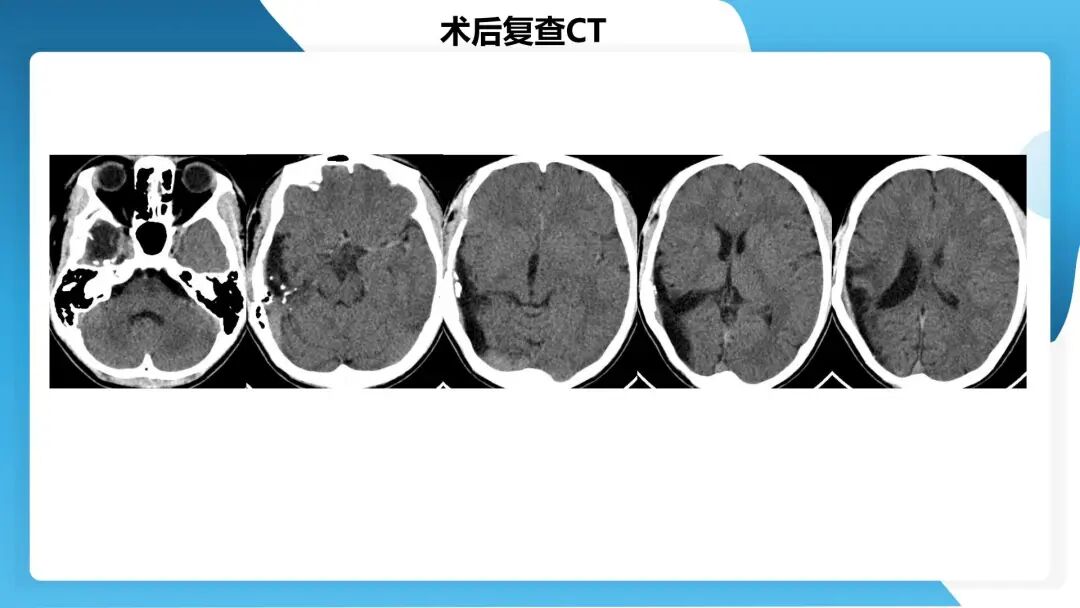

《「痫停」信步》癫痫治疗病例荟萃第四十四期---颞前叶及脑软化灶切除治疗难治性癫痫一例